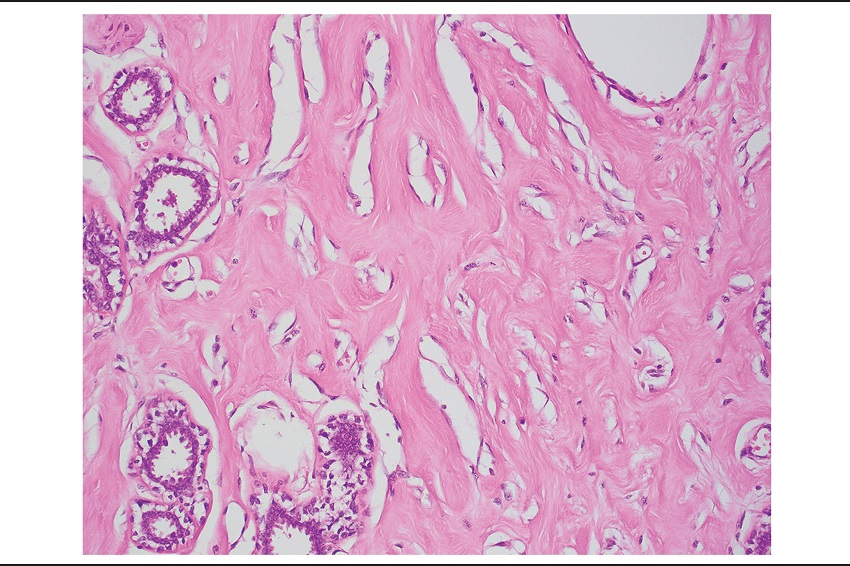

Upon examination by light microscopy, the tumor was composed of a densely collagenous stroma containing numerous anastomosing slit-like spaces, which appeared almost empty and intermixed benign breast ducts and lobules (Figure 1). Stromal spindle cells bordering these spaces resembled endothelial cells. Their nuclei were attenuated, lacked atypia and had no mitotic activity (Figure 2). The spaces were empty. These findings were diffusely and homogeneously seen throughout the whole tumor, which did not contain adipose tissue. The epithelial component comprised breast ducts and lobules, which in some areas had a normal appearance and in others, fibroadenomatoid changes with compressed ducts. The stroma was abundant and predominated over the epithelial component. Focal usual ductal hyperplasia and ductal dilatation were present. Stromal myxoid change were seen (Figure 3). Some areas had abundant edematous loose stroma with few intervening epithelial elements (Figure 4). The presence of these two latter features, along with a predominance of stroma led to an initial diagnosis of benign phyllodes tumor by the general surgical pathologist.

Microscopically, PASH is composed of benign breast parenchyma with an admixture of stroma and epithelial structures. The lesion is defined by the presence of complex often anastomosing spaces involving both intralobular and interlobular stroma, which is typically expanded and densely collagenous. Myofibroblasts line the spaces in a discontinuous fashion, resembling endothelial cells. These cells often have elongated bland nuclei with no atypia or mitotic activity. The stromal component is often increased with wider separation of ducts and lobular units when compared to the usual arrangement. Collagenization of intralobular stroma with duct attenuation commonly leads to a fibroadenomatoid appearance, which was seen in this case, and likely represented the feature that, along with the large tumor dimension, abundance of stroma and myxoid changes, led to an erroneous initial interpretation of benign phyllodes tumor. Usual ductal hyperplasia and ductal dilatation are common in PASH, and both findings were present in this case.